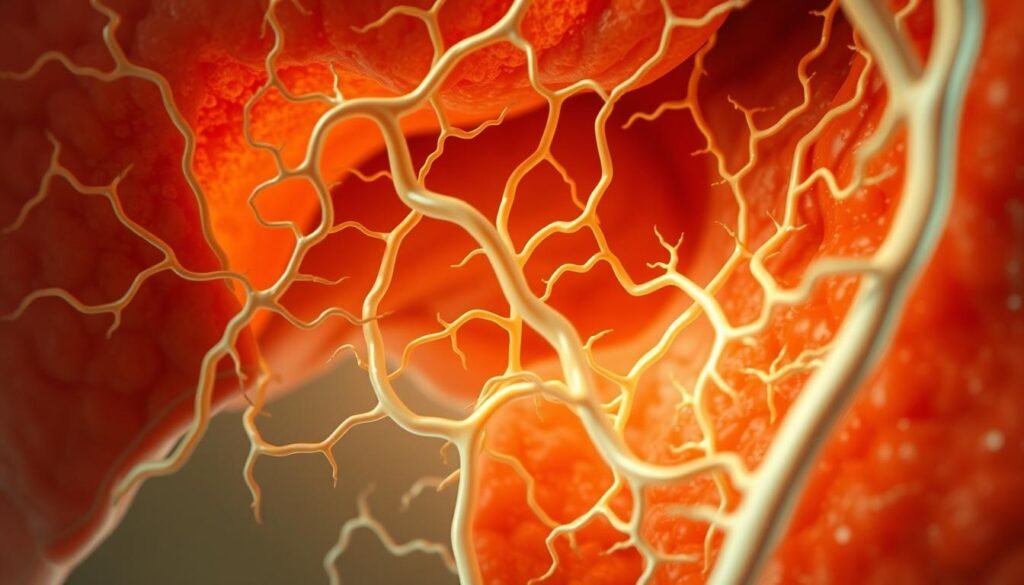

Here’s the deal: the hepatic artery brings oxygen-rich blood (think of it as fresh air for your cells), while the portal vein carries nutrient-packed blood straight from your intestine. They merge at the liver like highways meeting at a mega-rest stop. For real, this part of your body is busier than a lunch rush at a food court.

Let’s talk bile—a greenish liquid that’s basically your body’s dish soap. When you eat fries, bile breaks down fats so your intestine can absorb them. Meanwhile, liver cells work like tiny factories, converting substances into usable products (like turning apple juice into energy). And get this: they sort vitamins from waste smoother than a stage manager organizing props for a play.

Let’s break it down. The hepatic artery acts like a fresh-air supplier, pumping oxygen to keep things lively. Meanwhile, the portal vein delivers nutrient-packed blood from your snacks. Together, they’re the ultimate delivery duo—like Uber Eats for your cells.

Now, meet the bile ducts. These tiny tubes whisk away waste like yesterday’s lunch leftovers. Ever had a burger? Bile breaks down its fats faster than you can say “extra fries.” Without them, your cholesterol levels would party way too hard.